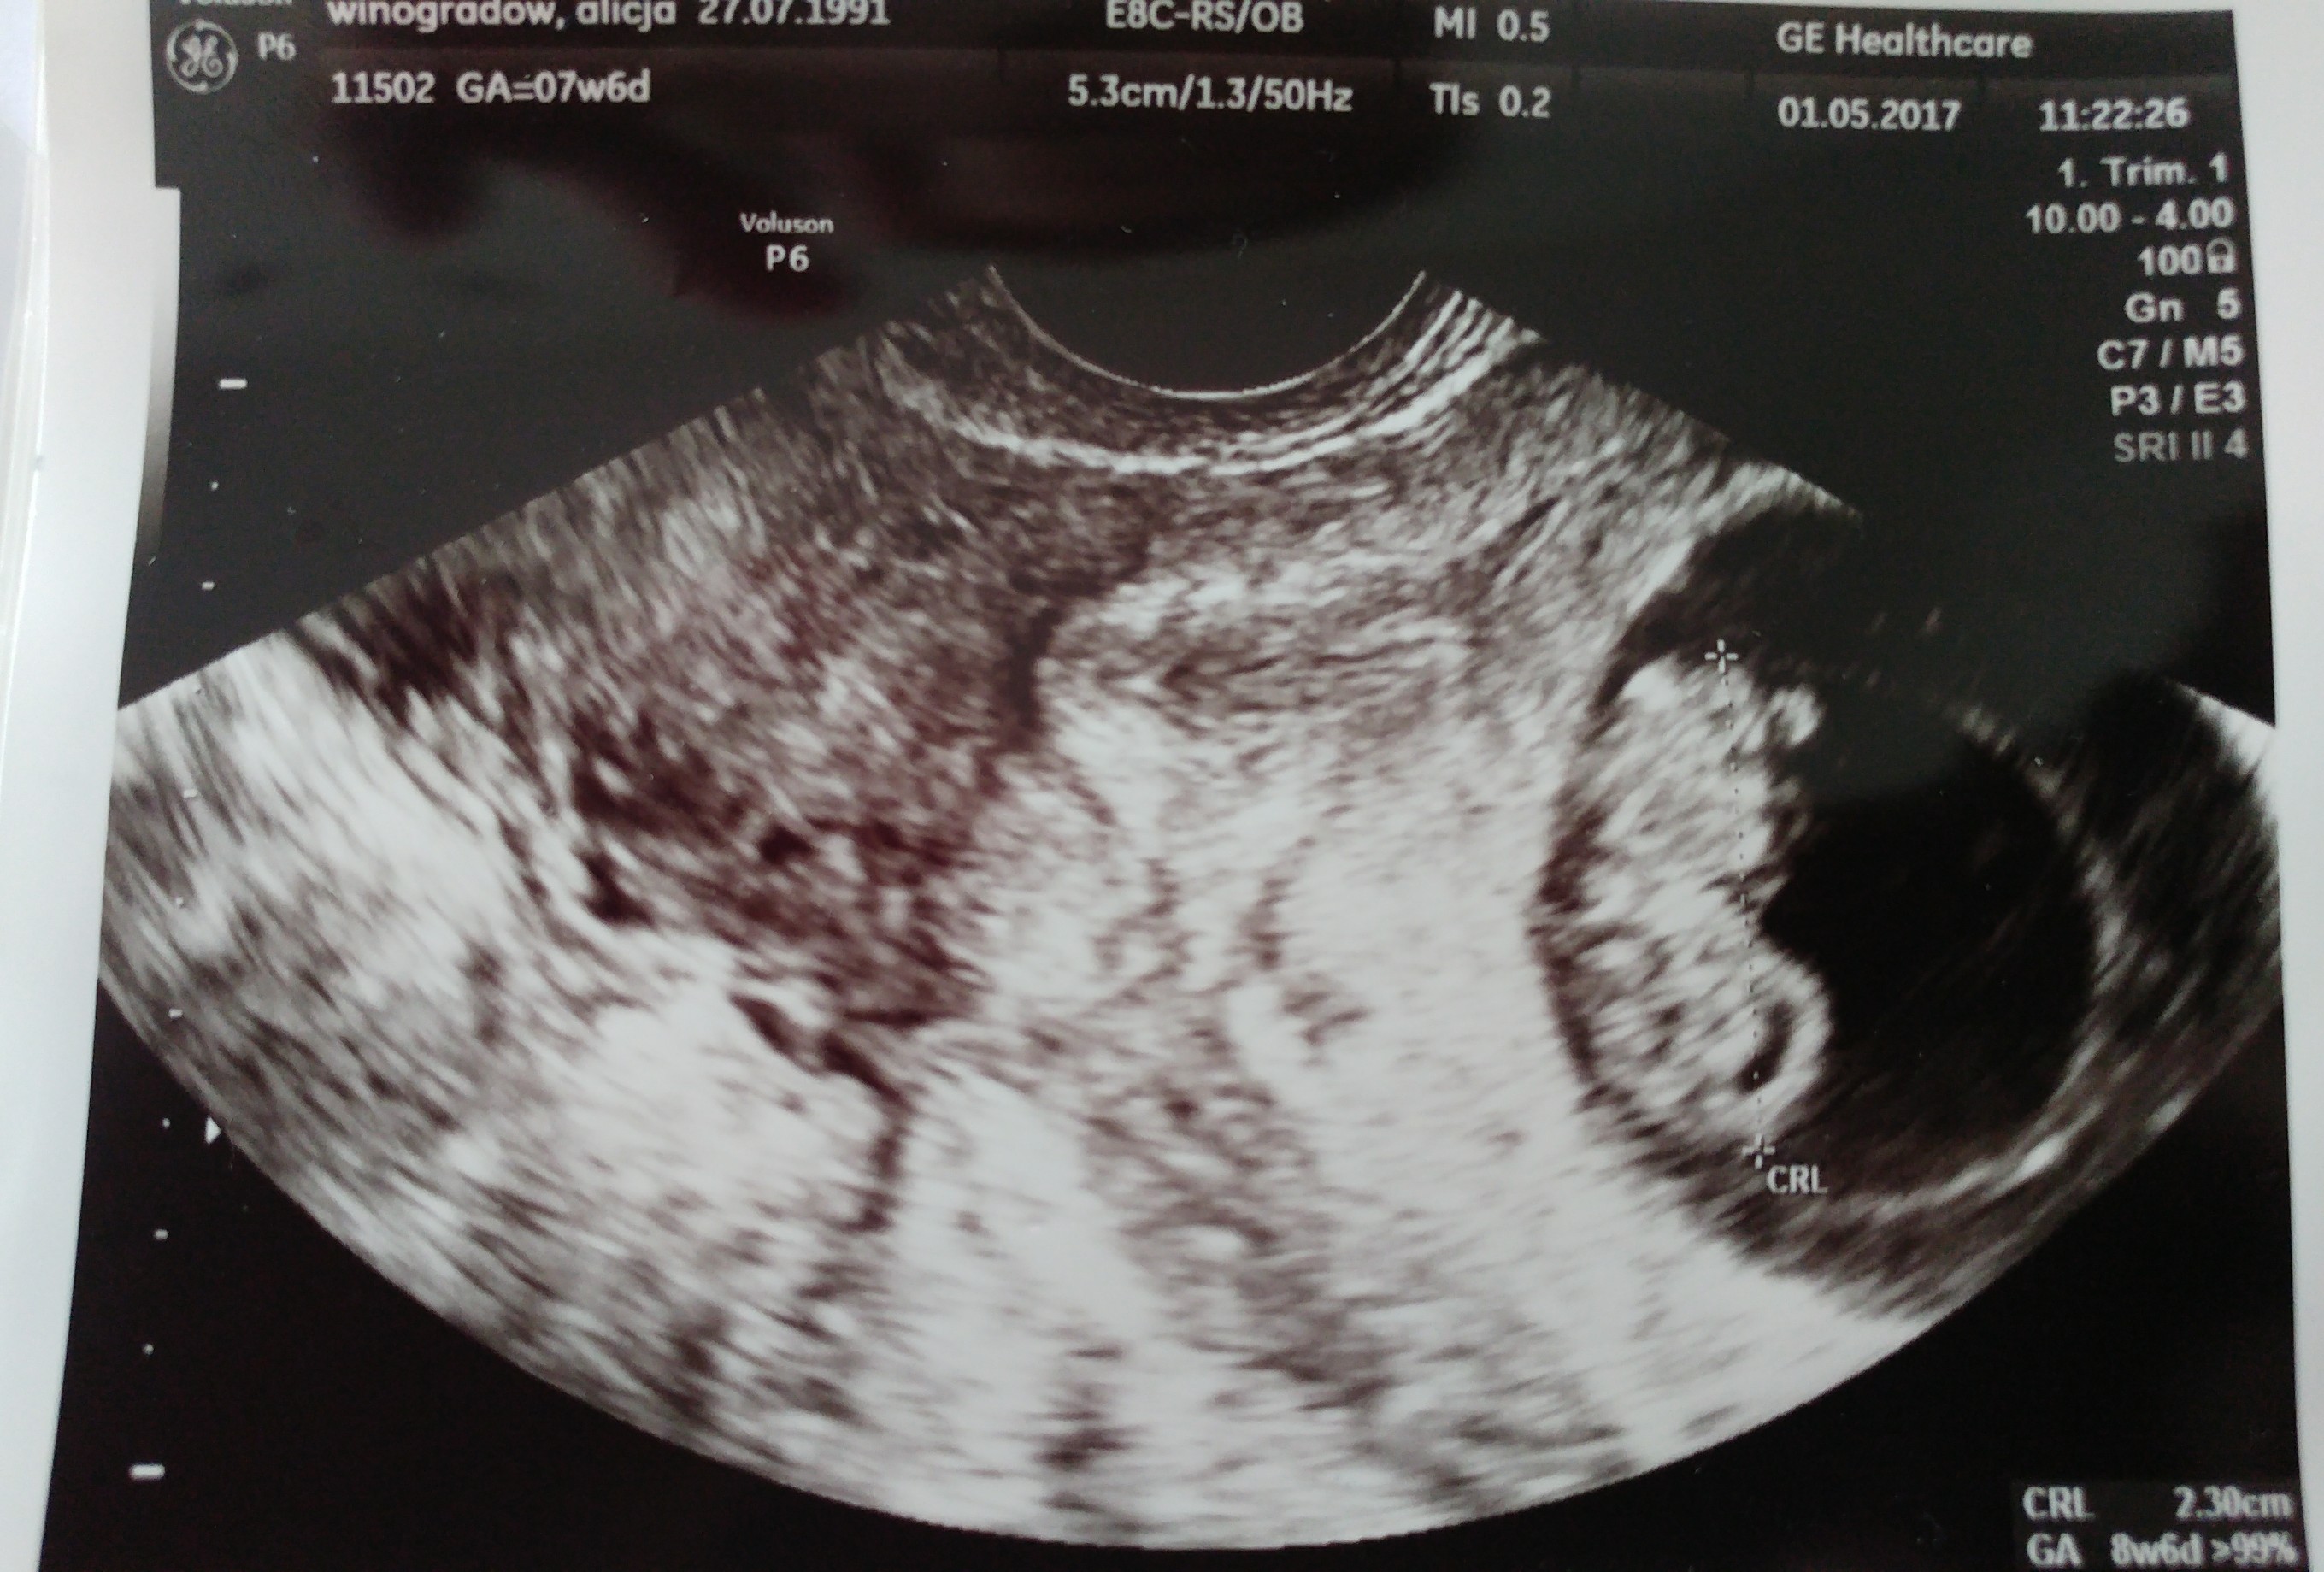

Super dzidzia gratulacje☺Zobacz załącznik 804782 Zobacz załącznik 804783 Zobacz załącznik 804784

My po wizycie

Na pierwszym zdjęciu widać rączkę, na drugim rączki, nóżki, na trzecim jest do góry nogami. Ruszał się, wręcz tańczył, serduszko tłucze jak szalone. Wszystko jest pięknie! Lekarz zachwycony, a my przeszczęśliwi![]()